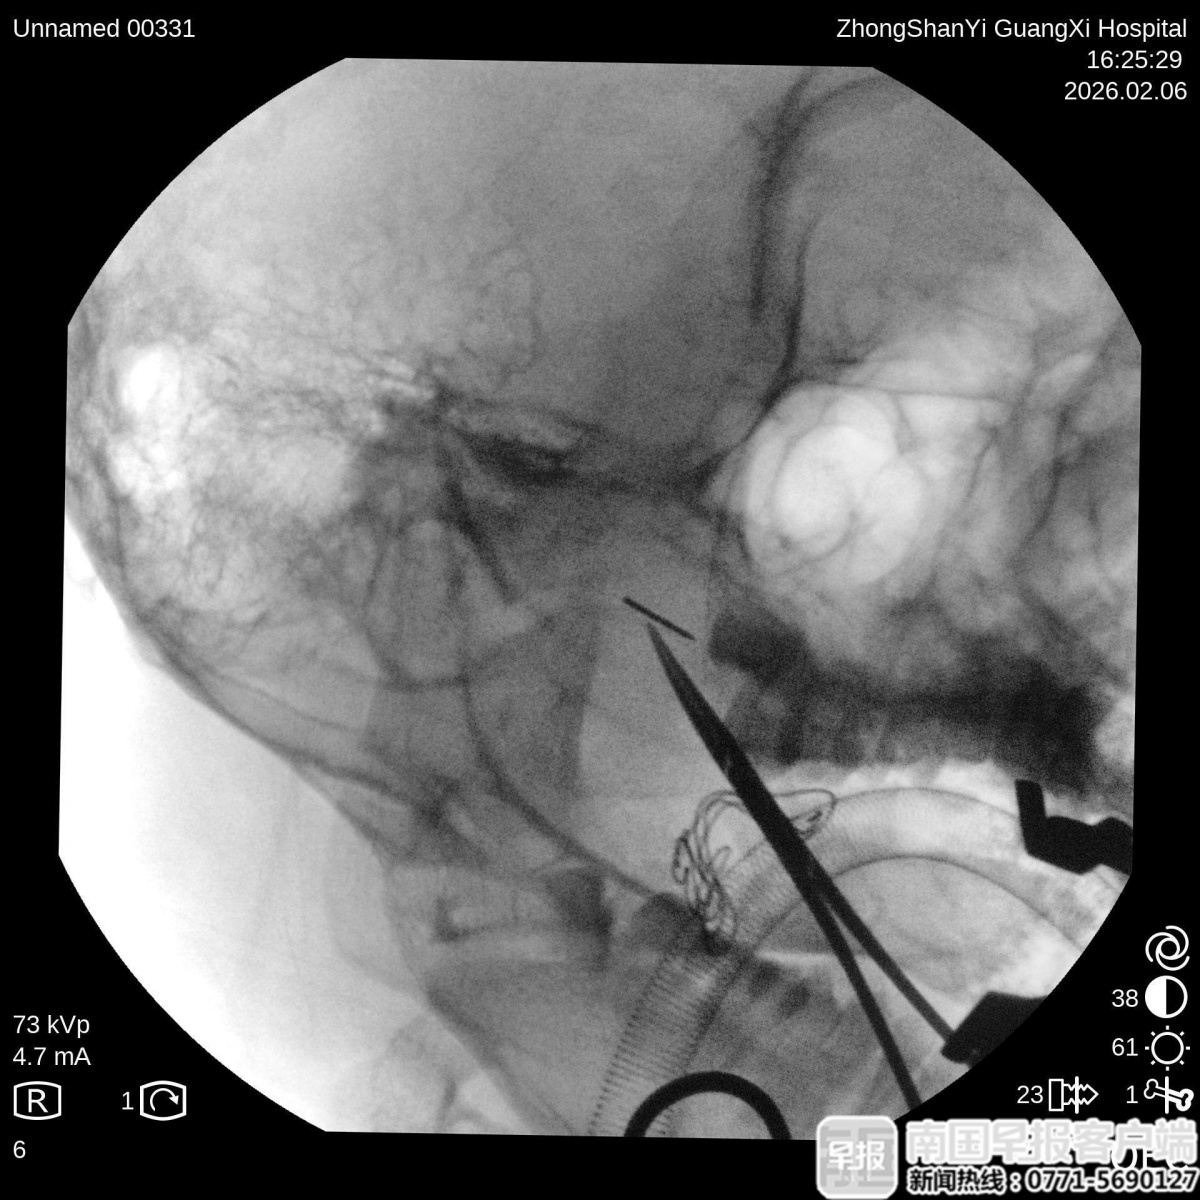

最终,团队为阿诺制订了个性化治疗方案,在气管插管全麻下,借助C臂X射线机多角度定位,为了防止断针跟随面部的软组织移动,团队使用高强度磁铁将断针固定,花了30分钟,经口实施手术成功取出断针。在手术过程中,同步开展面部伤口修复处理,既确保断针完整取出,又最大限度兼顾面部美观。“男孩正处于青春期,正是爱美的年纪,我们采用细如发丝一样的美容缝线,最大程度减少疤痕。”唐亮说。